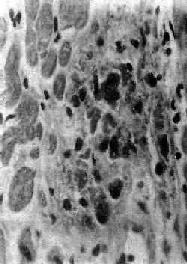

Aschoff  小体体积颇小,一般显微镜下才能看见(图8-19),多发生于心肌间质、心内膜下和皮下结缔组织;心外膜关节血管等处少见。在心肌间质内者多位于小 血管旁,略带圆形或梭形,其中心部为纤维素样坏死灶,周围有各种细胞成分:①Anitschkow细胞:胞浆丰富,嗜碱性,核大,呈卵圆形、空泡状。染色 质集中于核的中央,核的横切面状似枭眼;纵切面上,染色质状如毛虫。②Aschoff巨细胞(Aschoff giant cell):含有1~4个泡状的核,与Anitschkow细胞相似,胞浆嗜碱性。以上两种细胞的来源尚有争论,但现代标记技术证明其为巨噬细胞源性。③ 小体内还有少量淋巴细胞(主要为T细胞)和个别中性粒细胞。此期经过约2~3个月。

图8-19 Aschoff小体

主由Anitschkow细胞、Aschoff巨细胞和淋巴细胞等组成,中心部常有纤维素样坏死物